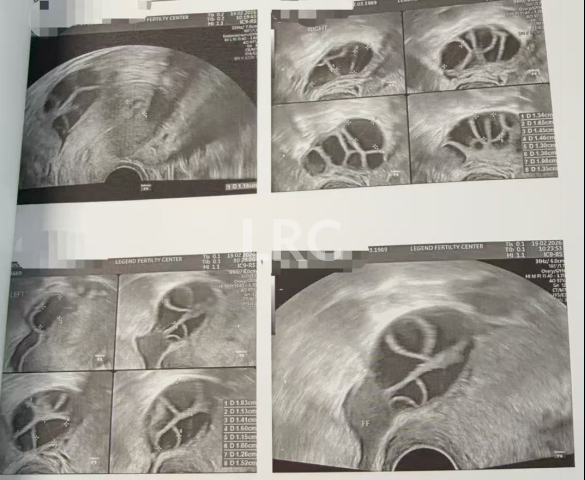

月经第二天 促排第一天

阴超检查:基础卵泡 18 颗

- 右侧卵泡 10 颗 (4-7mm)

- 左侧卵泡 8 颗 (4-6mm)

激素水平检查:

- 促黄体生成素 5.41 miu/ml

- 雌二醇 21.00 pg/ml

- 促卵泡生成素 5.17 miu/ml

促排第三天

阴超检查(只数能用卵子):

- 右侧卵泡 9 颗 (8,8,7,7,7,6,6,5,4mm)

- 左侧卵泡 5 颗 (8,8,7,6,5mm)

- 促黄体生成素 3.71 miu/ml

- 雌二醇 123.00 miu/ml

子宫内膜厚度:5 mm

促排第五天

阴超检查:

- 右侧卵泡 10 颗 (12,12,11,11,11,11,11,11,10,10mm)

- 左侧卵泡 8 颗 (12,12,11,11,11,10,10,10mm)

- 促黄体生成素 2.75 miu/ml

子宫内膜厚度:8.00 mm

促排第七天

- 右侧卵泡 9 颗 (17,17,15,15,14,14,13,13,12,11mm)

- 左侧卵泡 8 颗 (15,15,14,14,13,13,13,12,11,10mm)

- 促黄体生成素 4.18 miu/ml

- 雌二醇 2276.00 pg/ml

子宫内膜厚度:11.80 mm